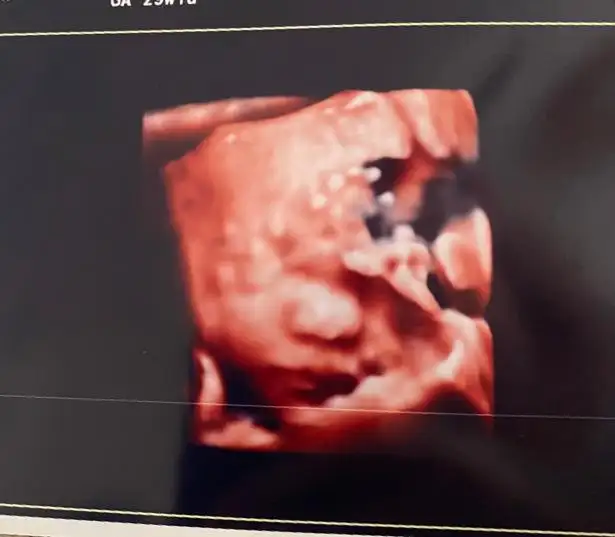

Sonbahardagel Sonbahardagel Z zerdecalim Teach_Mavi Teach_Mavi Melikeben Melikeben dr alttan bakti bi suruntu aldi akinti bu dedi dönemsel olabilir diyerek fitil verdi 1 hafta sonra tekrar gelmemi istedi cok sagolun kizlar dun gece gece aksiyon yasadik bebek suyu gayet yerindeymis 1.350 gr 38 cm olmus 🙏🙏🙏🙏

Eklentiler

• IMG-20230619-WA0002.webp

IMG-20230619-WA0002.webp

10,1 KB · Görüntüleme: 74

• 20230619_144052.webp

20230619_144052.webp

16,1 KB · Görüntüleme: 83